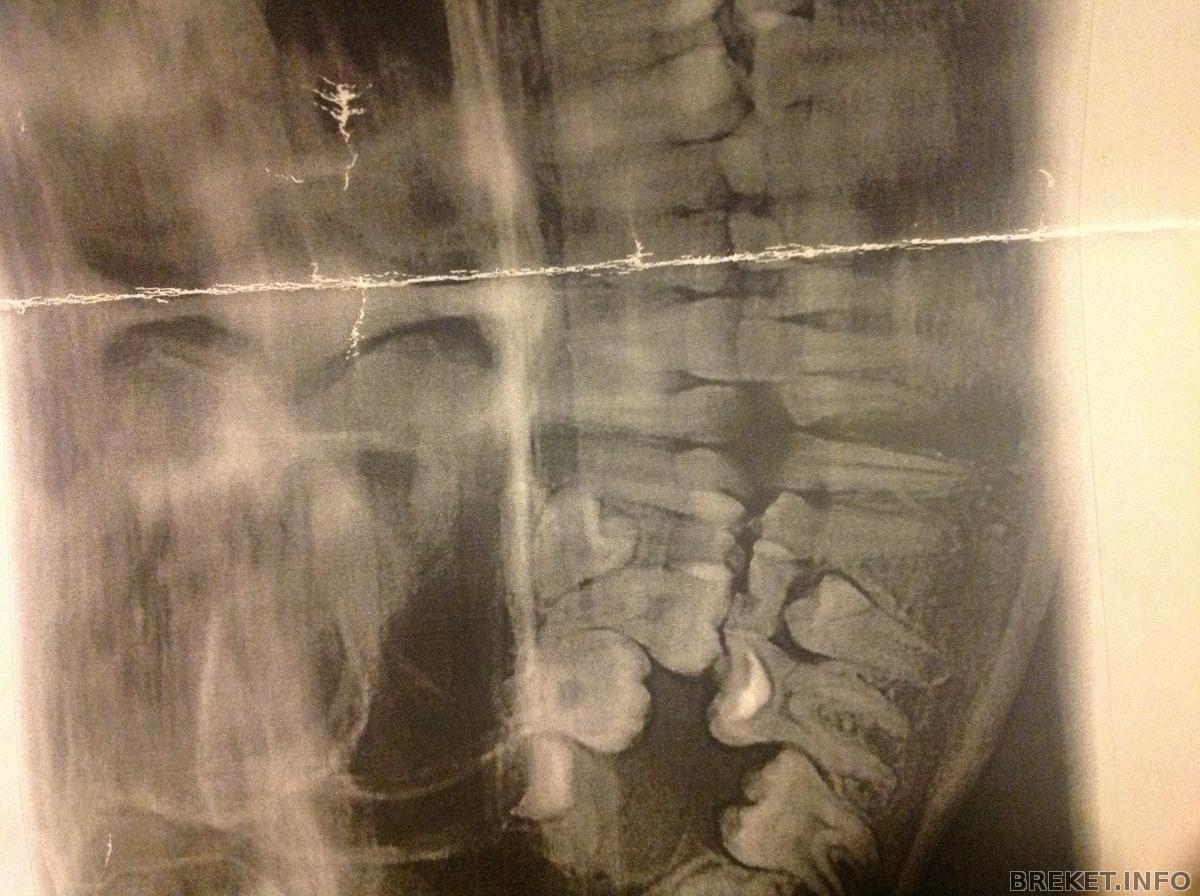

Я начала волноваться!тут снимки. Справа(слева для вас) зуб который находится совсем не в том положении.Мне начали рассказывать (на сайте) об операциях во многих таких случаях как там что то вырезают.нет на операцию я не пойду!Может все там нормально.Сейчас в этом промежутке разьединяются зубы,думаю то что это этот зуб будет вставать на место.Вух очень надеюсь

image.jpg